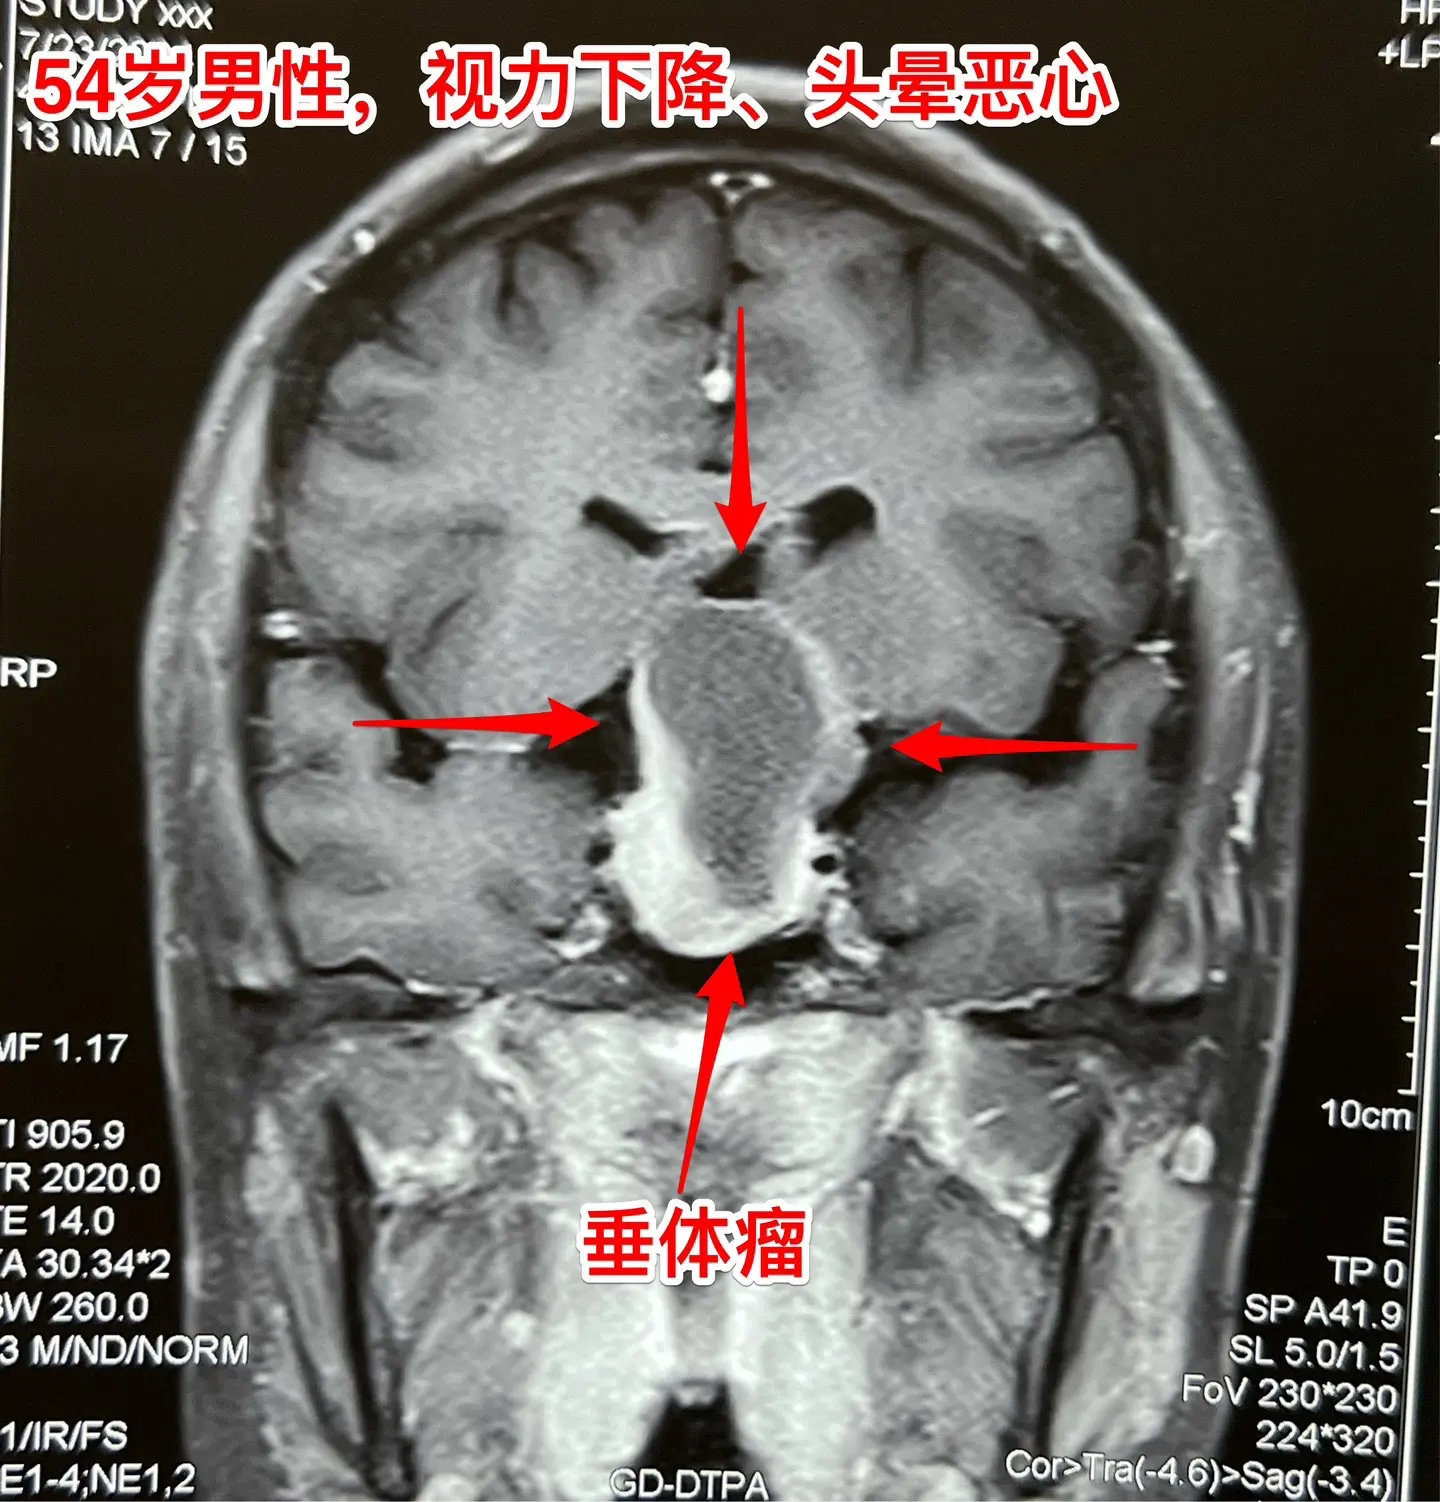

中元节是不是不适合作手术?昨天8月18号是中元节,我们科在上周提前安排在这一天作一台垂体瘤手术,那个时候我还没有想到这一天是中元节。 患者的女儿提到这日子不太好,是中元节,我才意识到的确不太合适。我就说,不行就在8月19日晚上作。这个女儿又说不行,因为8.19是病人的生日!我说如果这样的话只能往后推了,因为前面的手术都排满了。 患者女儿和家人商量了之后还是决定在8.18日作手术,因为之前患者为了排查冠心病,已经耽误了好几天时间,为了能缩短住院时间,他们只好选择8.18这个日子。 患者家属下定决心了,我心里却担心起来了!心里有隐隐的不安和恐惧,但是也不敢告诉病人。 昨天的手术很顺利,手术后我一直在医院等病人完全清醒了,作完了头部CT,结果很满意。在确保病人平安无事了我才敢离开医院。唯恐出现意外! 今天查看病人,病人精神好,自诉视野缺损情况有改善。我彻底放下心来了!